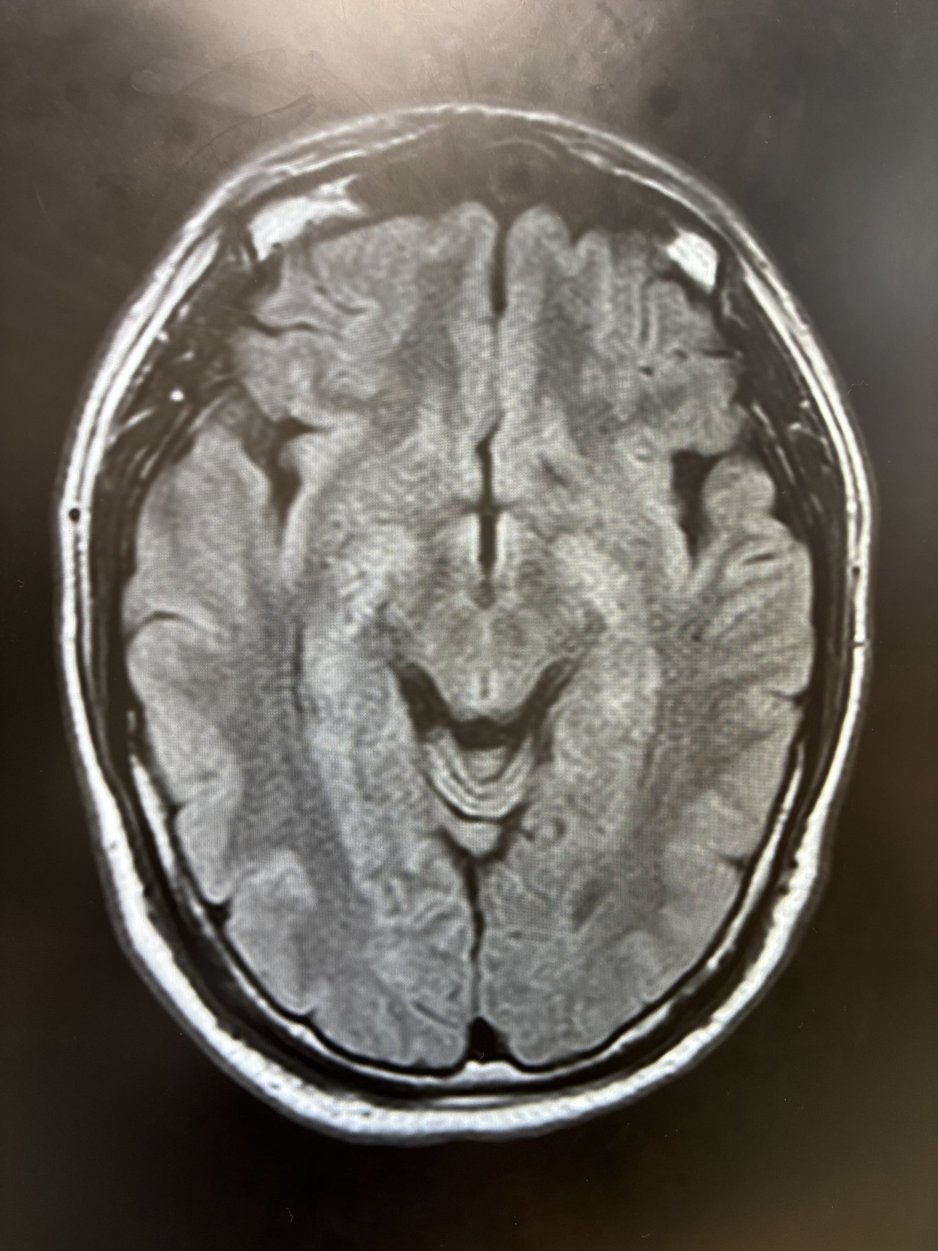

さすがに怖いので、翌日すぐにMRIを撮って診断を受けて来たので、ご安心ください。

ご覧ください。シワ一つ無い綺麗な脳でしょ?